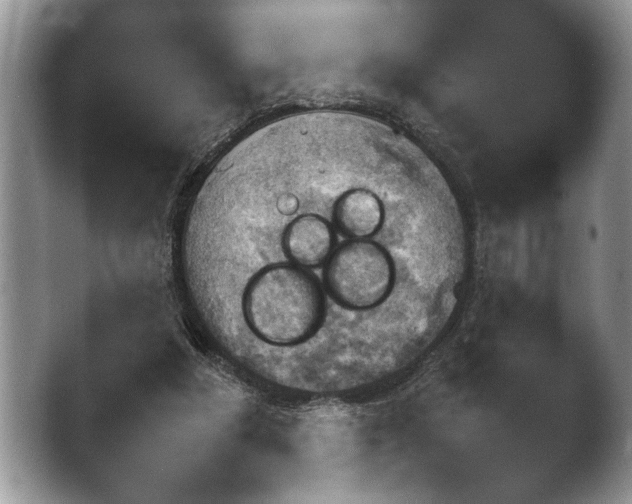

Image 420552

Image Data